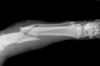

Over a median observation period for ascertainment of incident fracture of 4.7 years in both groups, 3,524 incident fractures (118 per 10,000 person-years) occurred in participants with urolithiasis compared with 29,590 in those without urolithiasis (101 per 10,000 person-years), the researchers reported online ahead of print in the Clinical Journal of the American Society of Nephrology.

Among male participants, urolithiasis was associated with a significant 13% overall increased risk of fracture. The risk of fracture associated with urolithiasis was significantly elevated among those aged 10–19 years (55% higher), 40–49 years (17% higher), 50–59 years (20% higher), and 80–89 years (25% higher). Among female participants, the fracture risk associated with urolithiasis was significantly elevated among those aged 30–39 years (55% higher), 40–49 years (45% higher), 50–59 years (32% higher), 60–69 years (25% higher), and 70–79 years (21% higher).